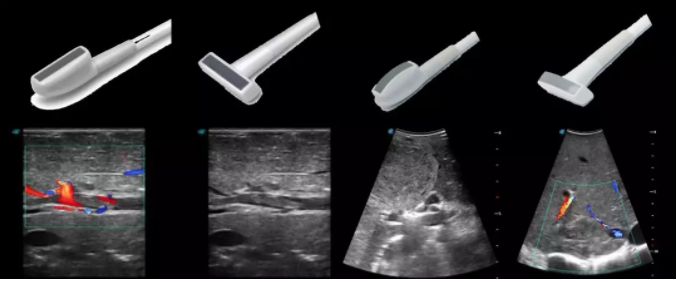

今天我們來講的是超聲探頭中的一些特殊探頭。

1生殖專用探頭

傳統(tǒng)腔內(nèi)探頭采用直柄設(shè)計,在搭配穿刺架使用時,手術(shù)空間小,不易操作;生殖專用的曲柄探頭,探頭柄采用彎曲成角度設(shè)計,可實現(xiàn)監(jiān)視、取卵兩不誤,搭載穿刺架時,可以清晰顯示穿刺針的進針過程、深度和位置,實時監(jiān)視取卵全過程,保障取卵操作精準與安全。

取卵臨床圖

2宮腔專用探頭

多數(shù)的生殖科醫(yī)生對于受精卵的植入采用憑經(jīng)驗操作或是使用傳統(tǒng)腔內(nèi)探頭引導,同樣存在手術(shù)空間小、受精卵放置位置不確定等風險。專業(yè)的宮腔專用探頭,配合專用的窺器使用,為醫(yī)生提供最大的手術(shù)視野。

胎移植臨床圖

6多種指夾式探頭

線陣/凸陣不同選擇,多種外形設(shè)計可以滿足適用于不同的臨床科室,滿足不同醫(yī)生的使用需求;

輕便小巧,方便持握;

防水、易消毒;

應用科室:手術(shù)室、肝膽外科、消化外科、腫瘤科、心胸外科、泌尿外科、婦產(chǎn)科等